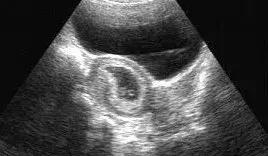

B超就是利用超声波了解体内结构的一种观察仪器。原理说白了很简单,就是发射超声波,超声波也是声音的一种,具有穿透能力,并且和所有的声音一样,遇到屏障会产生回声,不同的屏障回声的方式也不同,于是利用电脑收集这些回声,转化为相应的图像在屏幕上显示出来,起到观察内部脏器等作用。

那有人会问,既然彩超比B超好,为什么不把B超淘汰呢?首先,从检查费用来说,彩超检查费用比B超高。另外有些疾病只用黑白B超就能达到目的,例如像一般的胆结石、膀胱结石、肾结石、前列腺炎、肝囊肿、子宫肌瘤等疾病的复查都可以只用黑白超,还有像早孕的、想堕胎的患者,也只用黑白B超即可。